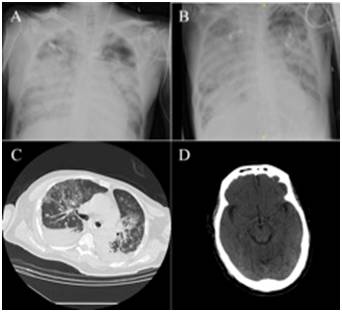

2017年1月7日(发病第1天)患者出现发热伴有咳嗽,随后出现气短。患者于1月10日(发病第4天)在当地医院就诊(图1),根据临床体征和CT检查,诊断双侧肺炎,取患者的咽拭子行流感病毒A/B床旁检验显示阴性,但因患者有禽类接触史,开始给予奥司他韦(75mg bid)治疗。在起病第6天,患者临床状况明显恶化,进展至严重呼吸衰竭,低氧血症(血氧饱和度78.6%)及昏迷,随后患者被转入重症监护室并行机械通气治,此时患者气管内抽吸物测H7N9病毒(实时定量逆转录PCR)显示阳性。起病第7天,患者心跳骤停,当天亦有轻微的胃肠道出血(但未行内镜检查),经过心肺复苏术和静脉注射去甲肾上腺,患者心跳恢复,胸片提示双肺浸润伴肺门阴影(图2 A),心脏大小和形态正常。因患者进展至严重急性呼吸窘迫综合征,停用奥司他韦,改用帕拉米韦(0.6GM i.v. qd),并开始使用抗菌素和体外膜肺氧合(ECMO),在使用ECMO治疗期间,患者氧合指数维持在200mmHg左右(图3),然而,在脱离ECMO治疗后,患者的临床状况持续恶化。生化检测结果显示在住院过程中,患者的白细胞总数、中性粒细胞计数、降钙素原、谷草转氨酶、肌酐、乳酸脱氢酶、尿素氮、D-二聚体增高,血红蛋白水平持续低下。因肾功能恶化(起病第8天至14天),患者开始接受持续肾脏替代治疗。气管内抽吸物病毒载量从第16天开始下降,在第20天转阴(图3)。住院期间,患者继发了多重耐药菌铜绿假单胞菌和鲍曼不动杆菌感染,同时在第11天血清中检测出巨细胞病毒(CMV)DNA。对于继发细菌感染,治疗上采用联合使用抗菌素方案,而对于继发CMV感染,在第32天开始使用更昔洛韦治疗。在第30天行肺部CT检查示多发双肺斑片状高密度病变,双侧胸腔积液(图2C)。同一天脑部CT扫描显示在左侧放射冠和右侧中心半卵圆边界不清低密度病变,最大约8mm×10mm,CT值为8 Hounsfield,提示腔隙性梗塞。双侧大脑半球对称,灰白质分明,脑实质未见明显病变,沟回无加深或增宽,脑室无扩张或畸形(图2 D)。反复行心电图检查未提示有心肌炎且多普勒心脏彩超提示心肌收缩功能良好。第40天,胸片仍提示双肺浸润伴肺门阴影(图2 B)。患者在第43天,患者因严重肺炎、急性呼吸窘迫综合征和多器官衰竭,最终死亡。

胸片提示双肺浸润伴肺门阴影(A: day 7; B: day 40);肺部CT检查示多发双肺斑片状高密度病变,双侧胸腔积液(C: day 30);头颅CT未见明显病变(D: Day 30)。